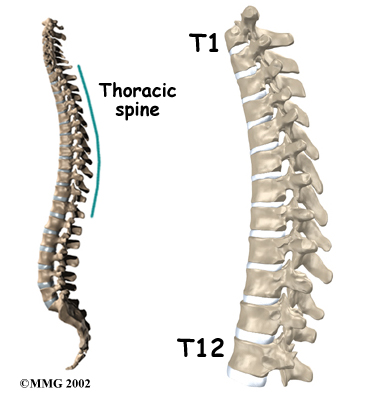

A healthy human spine has three gradual curves. From the side, the neck and low back curve gently inward. This is called a lordosis. The thoracic kyphosis (outward curve) gives the mid back its slightly rounded appearance. These normal curves help the spine absorb forces from gravity and daily activities, such as lifting.

The angle of normal kyphosis in the thoracic spine varies. The angle increases slightly throughout life both in women and men. During the growth years of adolescence, a normal curve measures between 25 and 40 degrees. In general, kyphosis tends to be more exaggerated in girls. If the curve angles more than 40 degrees in either boys or girls, doctors consider the kyphosis a deformity. Scheuermann's disease causes the thoracic kyphosis to angle too far (more than 45 degrees).

The 12 thoracic vertebrae are numbered from T1 to T12. The main section of each thoracic vertebra is a round block of bone, called the vertebral body. A ring of bone attaches to the back of the vertebral body. This ring surrounds and protects the spinal cord.

Scheuermann’s disease usually produces kyphosis in the middle section of the thorax (the chest), between the shoulder blades. Sometimes, however, it can cause kyphosis in the lower part of the thoracic spine, near the bottom of the rib cage.